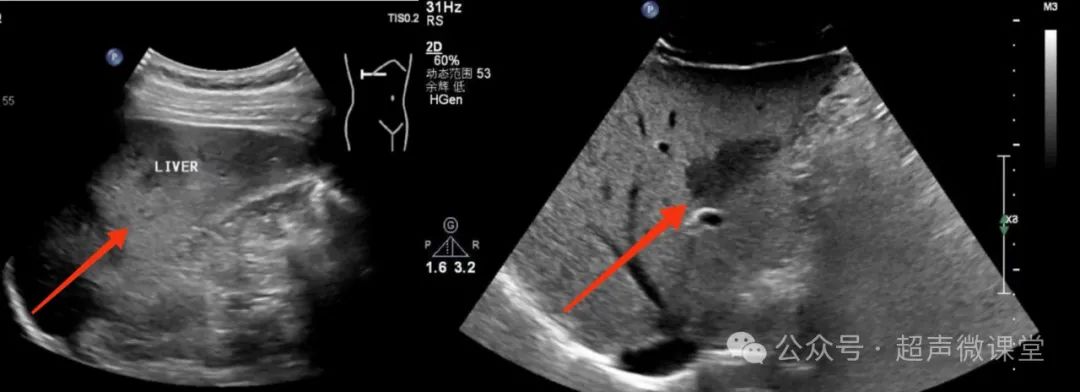

脂肪肝—"后段声衰减"图10 脂肪肝—"衰减"另外一个超声可以诊断的

局限性脂肪肝超声表现为,肝内回声增强局限于某叶或局部,而其他肝